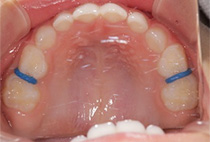

20代女性の患者さま。

八重歯の見た目が気になってご来院されましたが、実は顎の痛みや開口障害など、顎関節症の症状もありました。

そのため、かみ合わせと顎関節症の治療を同時に行ったにもかかわらず、2年間で治療が終了。

かみ合わせが整い咬筋の過緊張も改善しました。咬筋の肥大も治ってフェイスラインがすっきりしました。

最終的には美しい歯並びと、安定した痛みのないかみ合わせが実現しました。

八重歯が気になる

叢生、顎関節症、開口障害

20代女性

矯正治療2年

24回

唇側矯正

矯正:1,161,600円+毎月調整量:6,050円

しっかり前歯を下げるために、インプラントアンカーを使用してコントロールしました。

かみ合わせが整うと咬筋の過緊張が改善。

過緊張による筋肉肥大も改善しフェイスラインもすっきりしました。